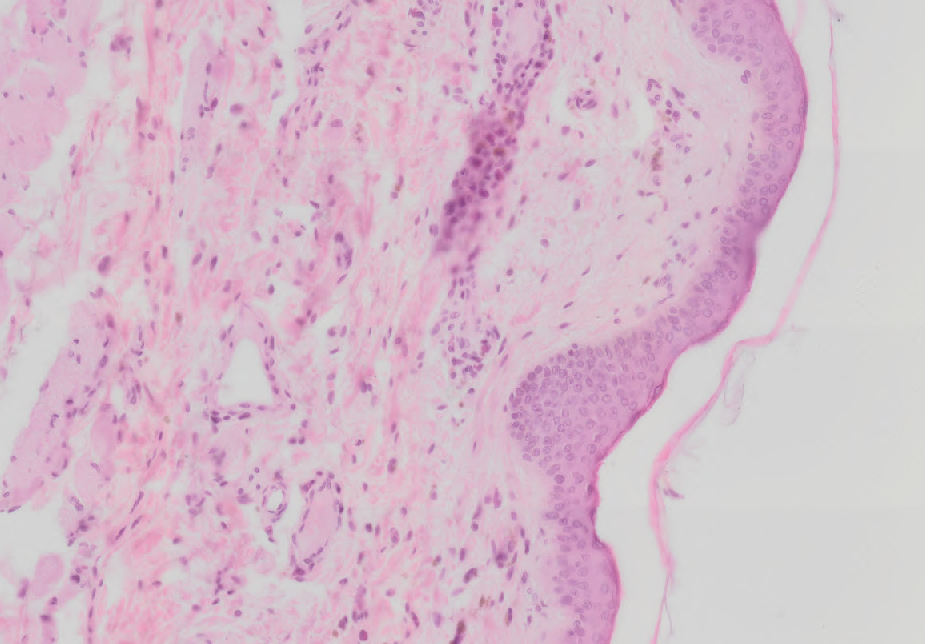

13 Which of following descriptions matches the specimen on the picture the best?

Mammary Gland before Lactation.png

Incomplete gland, contains ducts and a few alveoli only, embedded into the connective tissue

Incomplete gland, contains ducts and a few alveoli only, embedded into the adipose tissue

Tuboalveolar gland with rich branching, embedded into the connective tissue

Tuboalveolar gland with rich branching, embedded into the adipose tissue

14 On the picture, there is a thin type of skin stained with hematoxylin eosin. What is the thin eosinophilic strip over the epithelium od the right side of the specimen?

Thin Type of Skin.png

Some tissue from clothes, the specimen was harvested and processed really quickly

Incomplete stratum corneum; main part is often lost during the processing

Complete stratum corneum; this is why the skin is called thin type

Artifact from the staining